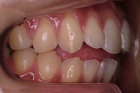

CASE1

前歯の歯並びが悪いのが一番気になります。

右側では良く噛めません↓(16歳/女性)

概要・担当医コメント:叢生・右側咀嚼障害↑

マルチブラケット装置/動的治療期間26ヶ月(23回)

/費用概算:60万円

高校の部活も矯正も両方頑張れたそうです。

上顎右側の小臼歯を1本のみ抜歯させていただき,あとは上下の歯列アーチ形態の修正にて矯正できました。